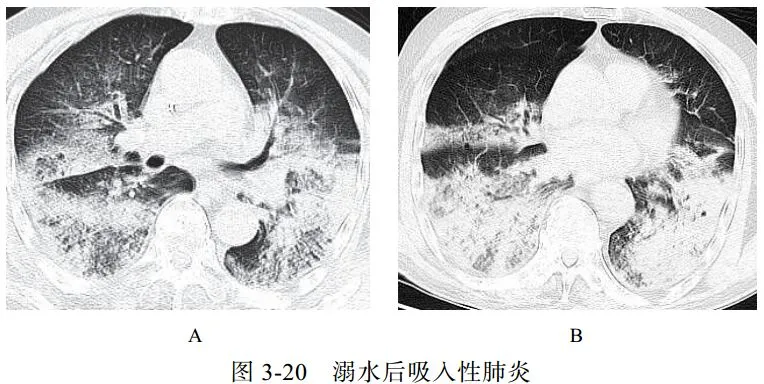

(六)吸入性肺炎

吸入性肺炎常见于慢性衰弱性疾病、咽和食管结构异常、全身麻醉等患者。吸入性肺炎可导致肺损伤或肺部炎症性疾病,如肺内节段性肺炎、支气管肺炎、肺脓肿和脓胸等。老年人存在隐性误吸

影像学表现:无明显特异性特征,需结合病史与临床表现来做出诊断(图 3-20)